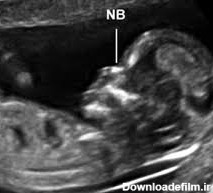

سونوگرافی NT مخفف nuchal-translucency به معنای فضای شفاف پشت گردن است و احتمال بروز نقایص کروموزومی را پیش بینی می کند. تمام جنین ها پشت گردنشان مایع دارند

کاربرد سونوگرافی NT - برای تشخیص برخی از ناهنجاری های مادرزادی مانند سندرم داون، ناهنجاری های کروموزومی و مشکلات قلبی مادرزادی، از این نوع سونوگرافی ...